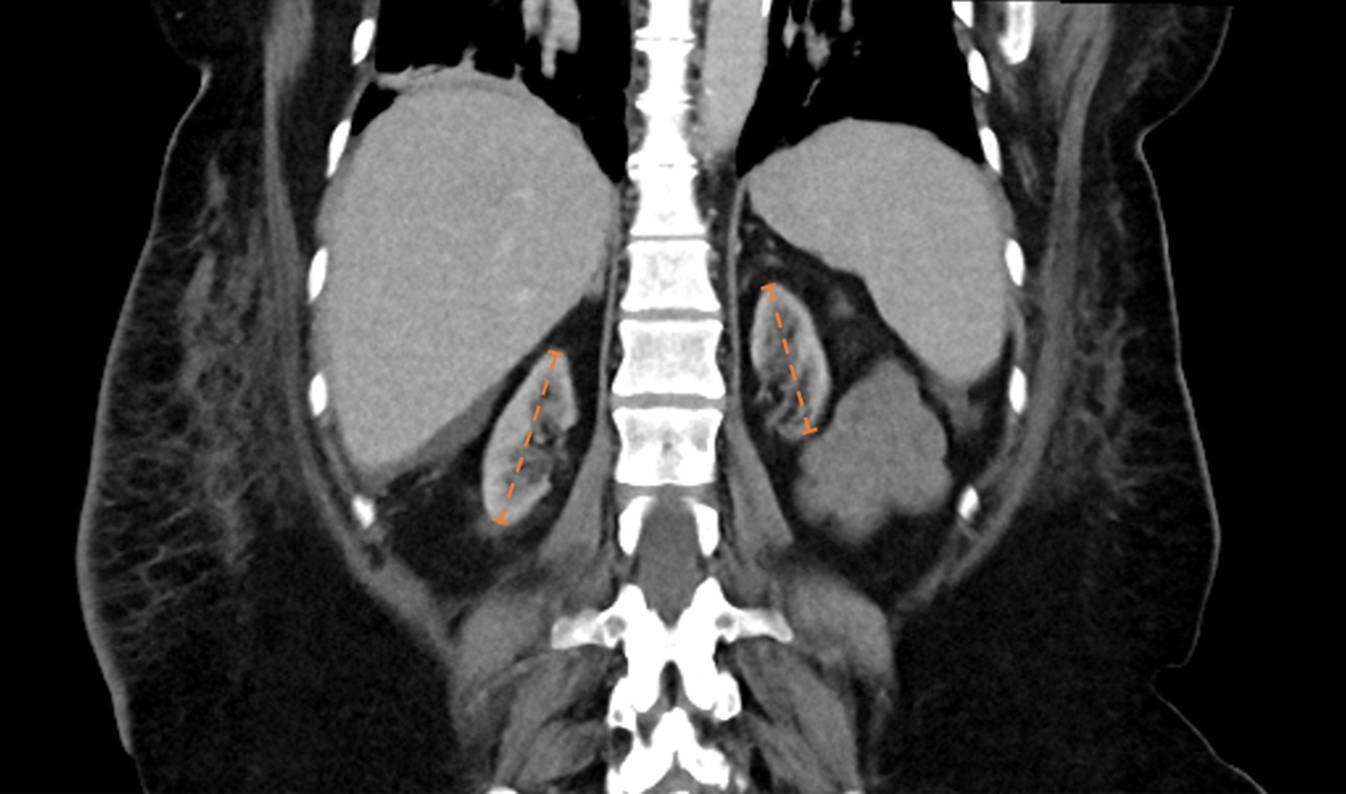

Die Patientin war im Jahr 2022 bei terminaler Niereninsuffizienz (CKD-Stadium 5, Dialysepflichtigkeit unklarer Genese seit 2014) einer Nierentransplantation unterzogen worden. Aufgrund von bilateralen Schrumpfnieren als Ausdruck einer lange bestehenden Nierenerkrankung im terminalen Zustand konnte eine Nierenbiopsie zur ätiologischen Sicherung nicht durchgeführt werden (siehe Abb. 1). Die aktuelle immunsuppressive Therapie umfasste Prednisolon (5 mg), den Calcineurininhibitor Tacrolimus (5 mg 1‑0-1) sowie den mTOR-Inhibitor Everolimus (3 mg 1‑0-1).

Abb. 1

Computertomographie des Abdomens nach erfolgter Nierentransplantation im Oktober 2022. Dargestellt sind bilaterale Schrumpfnieren, rechts 64 mm und links 58 mm im Längsdurchmesser